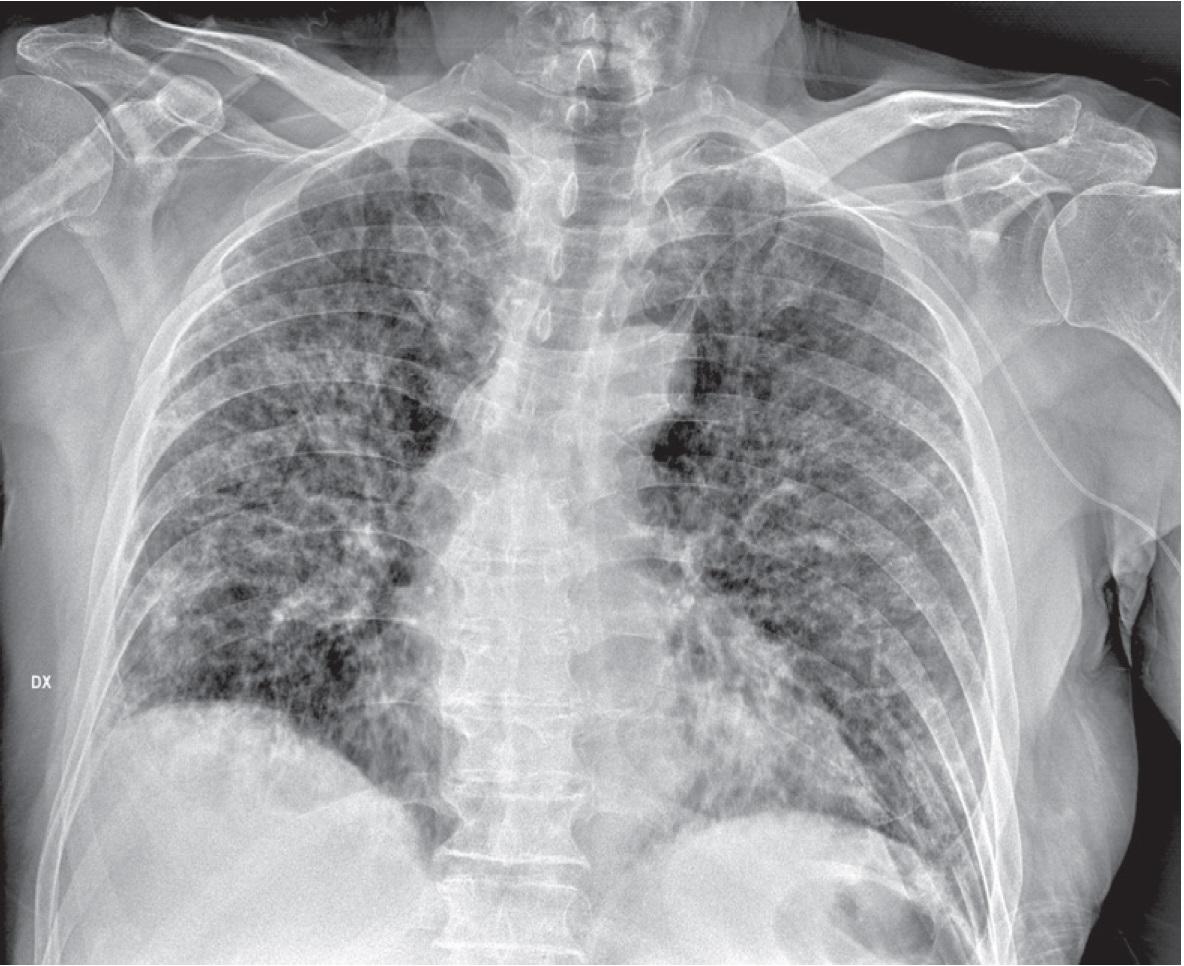

Suspected infected patient should be isolated, controlled, and diagnostic confirmation should be as quick as possible. Patients with mild symptoms should remain in home isolation, while patients with severe symptoms should be hospitalized, following the isolation guidelines.7 As for the first scenario, also in this case patient and healthcare staff should follow the same procedures concerning the use of masks, wear goggles or face shield, gloves and the distance of at least 6 feet if possible, avoiding direct contact with respiratory secretions, so as disinfection procedures for radiological equipment and rooms. In this scenario, it asks the radiologist to confirm the diagnosis of COVID-19. COVID-19 diagnosis is made by RT-PCR test, however radiological test is suggested for medical triage of suspected patients with moderate-severe clinical symptoms and with higher pre-test infection probability.8 The reported sensitivity of chest x-ray (CXR) for COVID-19 pneumonia is relatively low in the early phase of the disease and in mild cases (69%).48 Conversely, chest computed tomography (CT) shows greater sensitivity for early pneumonic change, disease progression, and alternative diagnoses; the administration of the intravenous contrast medium, is essential for the diagnosis of pulmonary thromboembolism.9 However, in Italy, to reduce the possibility of the spread of the infection, in accordance with the Italian Society of Radiology and Interventional Radiology (SIRM) guidelines, CXR is the first tool to be used in patients with suspected COVID-19 (see Figure 1 that shown a patchy consolidation and strip-like opacity in a patient with confirmed COVID-19 disease by RT-PCR).10 Since, portable equipment for performing the diagnostic investigation in the patient ‘s isolation room is the element that might favour CXR in selected patients, reducing the risk of COVID-19 infection and eliminating the risk related to the transport route to a CT scanner (Table 2).8

Man, 64 year. Chest x-ray shows patchy consolidation and strip-like opacities in a patient with confirmed COVID-19 infection by reverse transcriptase-polymerase chain reaction (RT-PCR).